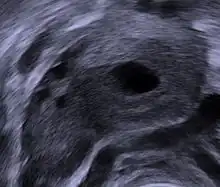

Le corps jaune (corpus luteum) est une formation temporaire[1], à l'intérieur de l'ovaire, qui résulte de la transformation du follicule de De Graaf (follicule mûr ou encore déhiscent) après expulsion de l'ovocyte lors de l'ovulation.

Ce corps jaune, qui se forme durant la phase lutéale (la troisième[2] étape du cycle ovarien), a pour fonction de sécréter de la progestérone (provenant du cholestérol sanguin) sous contrôle d'une hormone hypophysaire, la LH. La progestérone a pour rôle de maintenir la muqueuse utérine destinée à accueillir l'embryon lors de la nidation. En cas de non-fécondation de l'ovule, le corps jaune dégénère, se flétrit, entraînant avec lui une diminution de la sécrétion de la progestérone et finalement l'apparition des règles correspondant au début d'un nouveau cycle. Si l'embryon se fixe, le corps jaune va se maintenir et produire de la progestérone pendant le début de la grossesse, sous contrôle de la gonadotrophine chorionique humaine (hCG). Il disparaît vers le 3e ou 4e mois lorsque le placenta acquiert une autonomie suffisante.

Dans un premier temps, la membrane de Slavjanski disparaît, laissant pénétrer les capillaires sanguins des thèques au sein de la granulosa, ce qui entraîne une transformation des cellules folliculeuses. Ces dernières augmentent considérablement de volume et s'enrichissent en lipides (d'où leur aspect vacuolisé en technique banale ⇒ dissolution des graisses). Elles sécrètent un pigment légèrement jaune, la lutéine, responsable de la teinte jaune pâle du corps jaune sur un ovaire à l'état frais, c'est le phénomène de lutéinisation. En microscopie électronique s’observent sur ces cellules les caractères ultra-structuraux des cellules stéroïdogènes (c'est-à-dire un réticulum endoplasmique abondant, des gouttelettes lipidiques et des mitochondries à crêtes tubulaires). Ces cellules se nomment les grandes cellules lutéales ou cellules lutéiniques. Elles forment une couche épaisse et sécrètent la progestérone.

Des capillaires sanguins accompagnés de fibres conjonctives thécales ont traversé la granulosa et s'ouvrent dans l'ancienne cavité folliculaire, la remplissant d'un caillot sérofibrineux, le coagulum central. Ce coagulum est fait de fibrine et d’hématies.

Les cellules de la thèque interne, quant à elles, changent peu d'aspect et forment des petits cordons cellulaires bien vascularisés « nichés » dans les replis de la couche progestative. Ce sont les petites cellules lutéales ou cellules paralutéiniques et elles sécrètent alors des œstrogènes principalement, mais aussi des androgènes et de la progestérone.